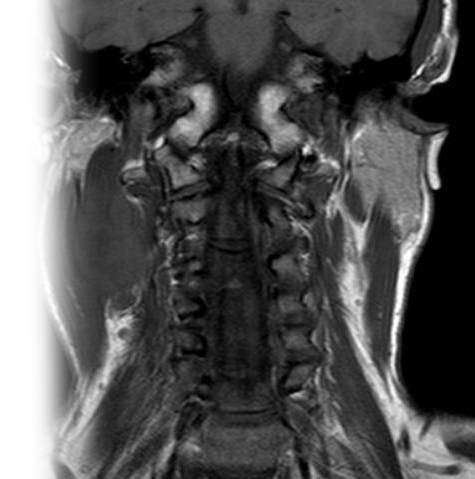

МРТ мягких тканей шеи с контрастом

Магнитно-резонансная томография мягких тканей шеи с контрастированием – важный метод исследования с введением контраста, который позволяет визуализировать мышцы, связки, сухожилия, подкожно-жировую клетчатку, щитовидную железу, лимфатические узлы, слюнные и околоушные железы.